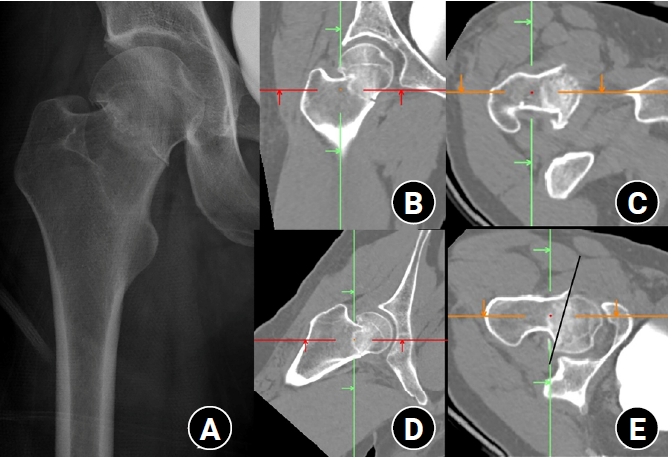

Although Pauwels biomechanical classification is in use nowadays, practical measurement of coronal verticality had lower reliability in preoperative radiographs due to projection errors and leg deformity during radiographic examination [11,16,17]. Considering that femoral neck fractures in non-older adults inevitably have significant displacement and comminution of fracture site, the conventional method to measure the PA is technically difficult in practice. Thus, we performed verticality measurements in multiple sites based on a previous study [11]. Through this imaging study, we would introduce how to apply Pauwels classification in practice after eliminating projection error of comminuted neck fracture in non-older adults. By using the software to allow free 360° rotations with magnification in any plane, this study has several interesting and practical findings. First, among six coronal images, the centerline image had the highest value of coronal PA. The coronal PA of the 1st central image was a mean value of 55.43°±13.79° and the 1st posterior images, mean value of 51.44°±11.13 (P=0.003). Second, CT scanning planes along the centerline of the femoral neck in coronal and axial planes could be used to measure the maximal fracture verticality without specialized software or equipment (Fig. 6). Third, fractures of the linear type in the coronal plane and trochanteric type in the axial type had higher verticality than other types. Thus, they were classified into the high verticality group.

Fig. 6.

A 38-year-old male patient presented with hip pain following a 3 m fall. (A) The initial plain radiograph revealed a femoral neck fracture. (B, C) The computed tomography (CT) plane parallel to the femoral neck centerline identified a convex fracture with a Pauwels angle of 45.1° in the coronal plane. (D, E) Reorientation of the CT plane along the femoral neck demonstrated a cephalad-type fracture with an axial verticality of 75.8° in the axial plane.